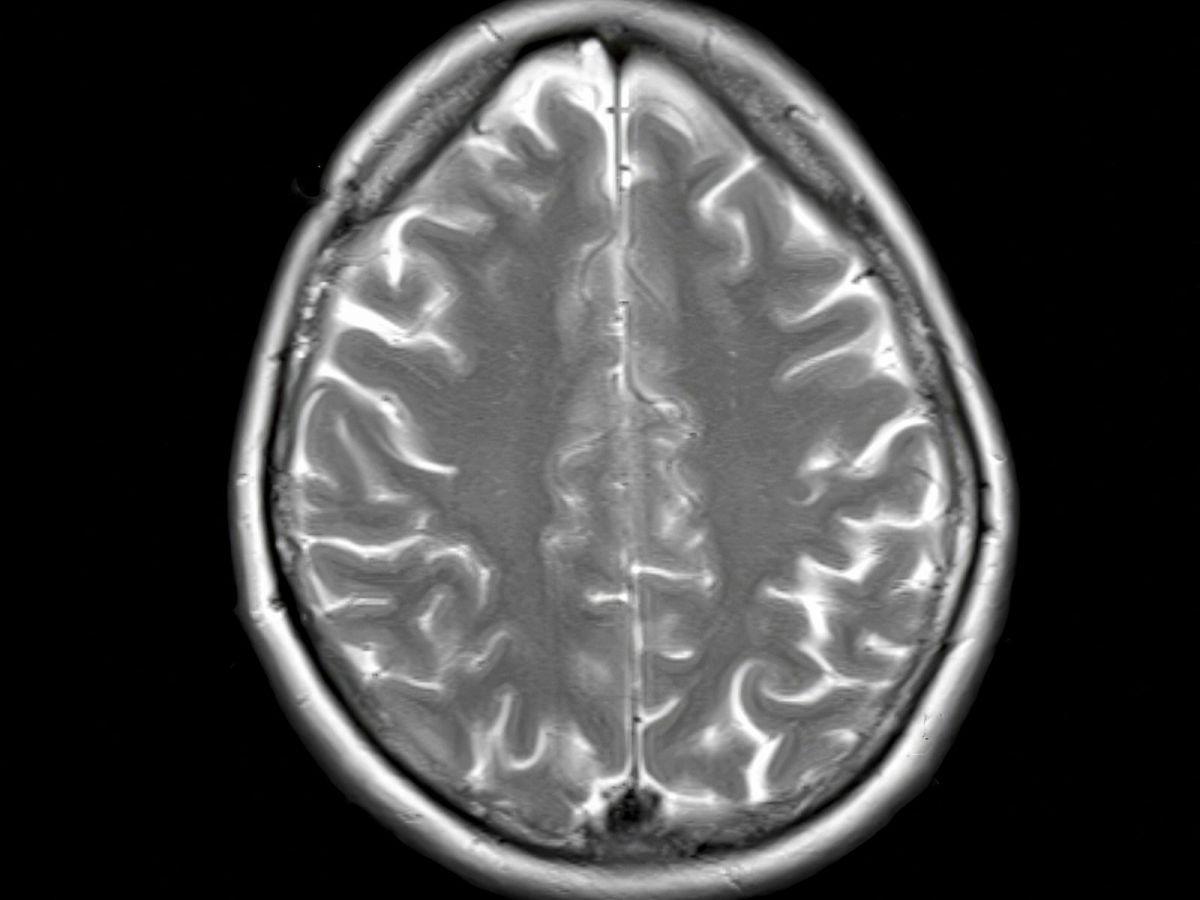

Africa-Press – Togo. Dans son ouvrage « Cortex », au fil de nombreux cas cliniques étonnants, le professeur de neurologie Richard Lévy invite à découvrir la façon dont le cortex façonne l’intelligence humaine.

Hypertrophiée chez notre espèce par rapport aux autres primates, cette écorce entourant le cerveau fonctionne comme une interface entre nos perceptions et notre capacité à choisir et à agir.